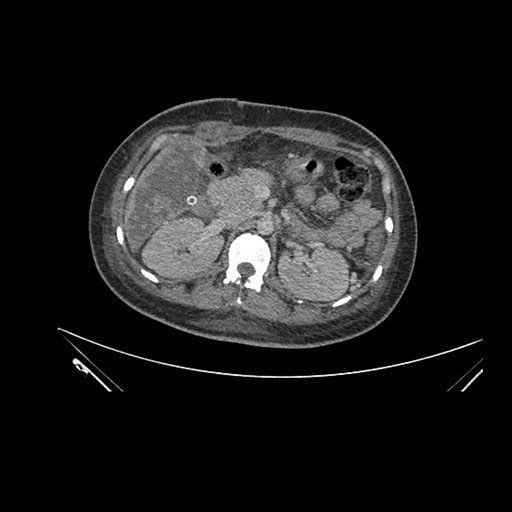

Imaging Analysis

Look through the patient's CT scan to identify any areas of concern for the necessary procedure.

Axial Arterial

Based on initial findings, which issue(s) would you be most concerned about?